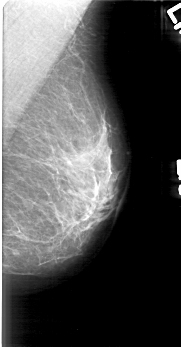

D_4166_1.RIGHT_MLO

D_4166_1.RIGHT_CC

RIGHT_MLO LINES 4906 PIXELS_PER_LINE 2836 BITS_PER_PIXEL 12 RESOLUTION 43.5 OVERLAY

RIGHT_CC LINES 4786 PIXELS_PER_LINE 2416 BITS_PER_PIXEL 12 RESOLUTION 43.5 OVERLAY